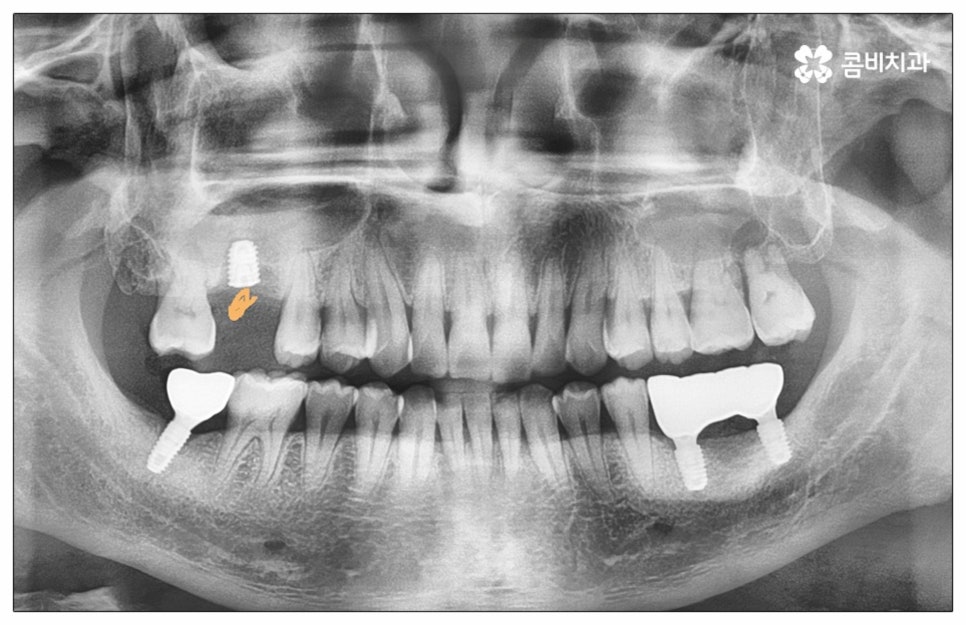

많이 대중화 되었다고 해도 임플란트 수술 자체가 술자의 숙련도에 크게 영향을 받는 복잡하고 고난도의 진료인 것은 틀림이 없기 때문에 담당 의료진이 해당 분야 임상 경험이 풍부한지, 뛰어난 기술력과 노하우를 가지고 있는지 꼼꼼하게 체크해 보실 필요가 있어요. 특히 노년층의 경우 당뇨, 고혈압 등 만성 질환을 앓고 있는 경우가 많아 혹시 상시 복용하고 있는 약이 있는지, 현재 환자 개개인의 상태는 어떤지, 사전 처치가 필요한 부분은 없는지 등등 수술 조건을 좀 더 까다롭게 평가한 후 환자분들과 이에 대해 충분히 상담하고 맞춤형 치료 계획을 세워 진행해야 하며 이를 위해 3D CT 와 같은 디지털 검진 장비를 통해 구강 내부 구조를 면밀하게 살피고 방대한 임상 데이터를 축적한 정품 임플란트 재료를 이용하여 연령이나 회복 정도를 살펴보면서 체력적 부담을 줄이는 방향으로 무리하지 않게 식립하는 것이 무엇보다 중요하다고 할 수 있습니다.

이때 추가 수술은 비급여 항목으로 건강보험임플란트 대상에서 제외되니 이에 대해서도 꼼꼼하게 살펴보시고 정밀 검진 후 담당 의료진과 자신의 상황에 대해서 충분하게 상담해 보시길 권유드리고 있습니다. 추가 수술의 대표적인 예로는 뼈이식 수술이 있는데요. 이것은 임플란트를 식립할 때 바탕이 되는 잇몸뼈의 높이나 폭, 밀도 등이 부족하다면 먼저 이를 보충해 주고 나서 임플란트를 심어주는 과정을 의미하며 같은 이유로 식립 성공률이나 장기적인 안정성을 높이기 위해 꼭 필요한 사전 처치, 즉 상악동 거상술 및 치주 질환 관련 수술 등을 먼저 해야 한다면 이 역시 추가 수술의 범주로 들어가니 자신의 상황에 대해서 상세하게 알아보실 필요가 있어요.